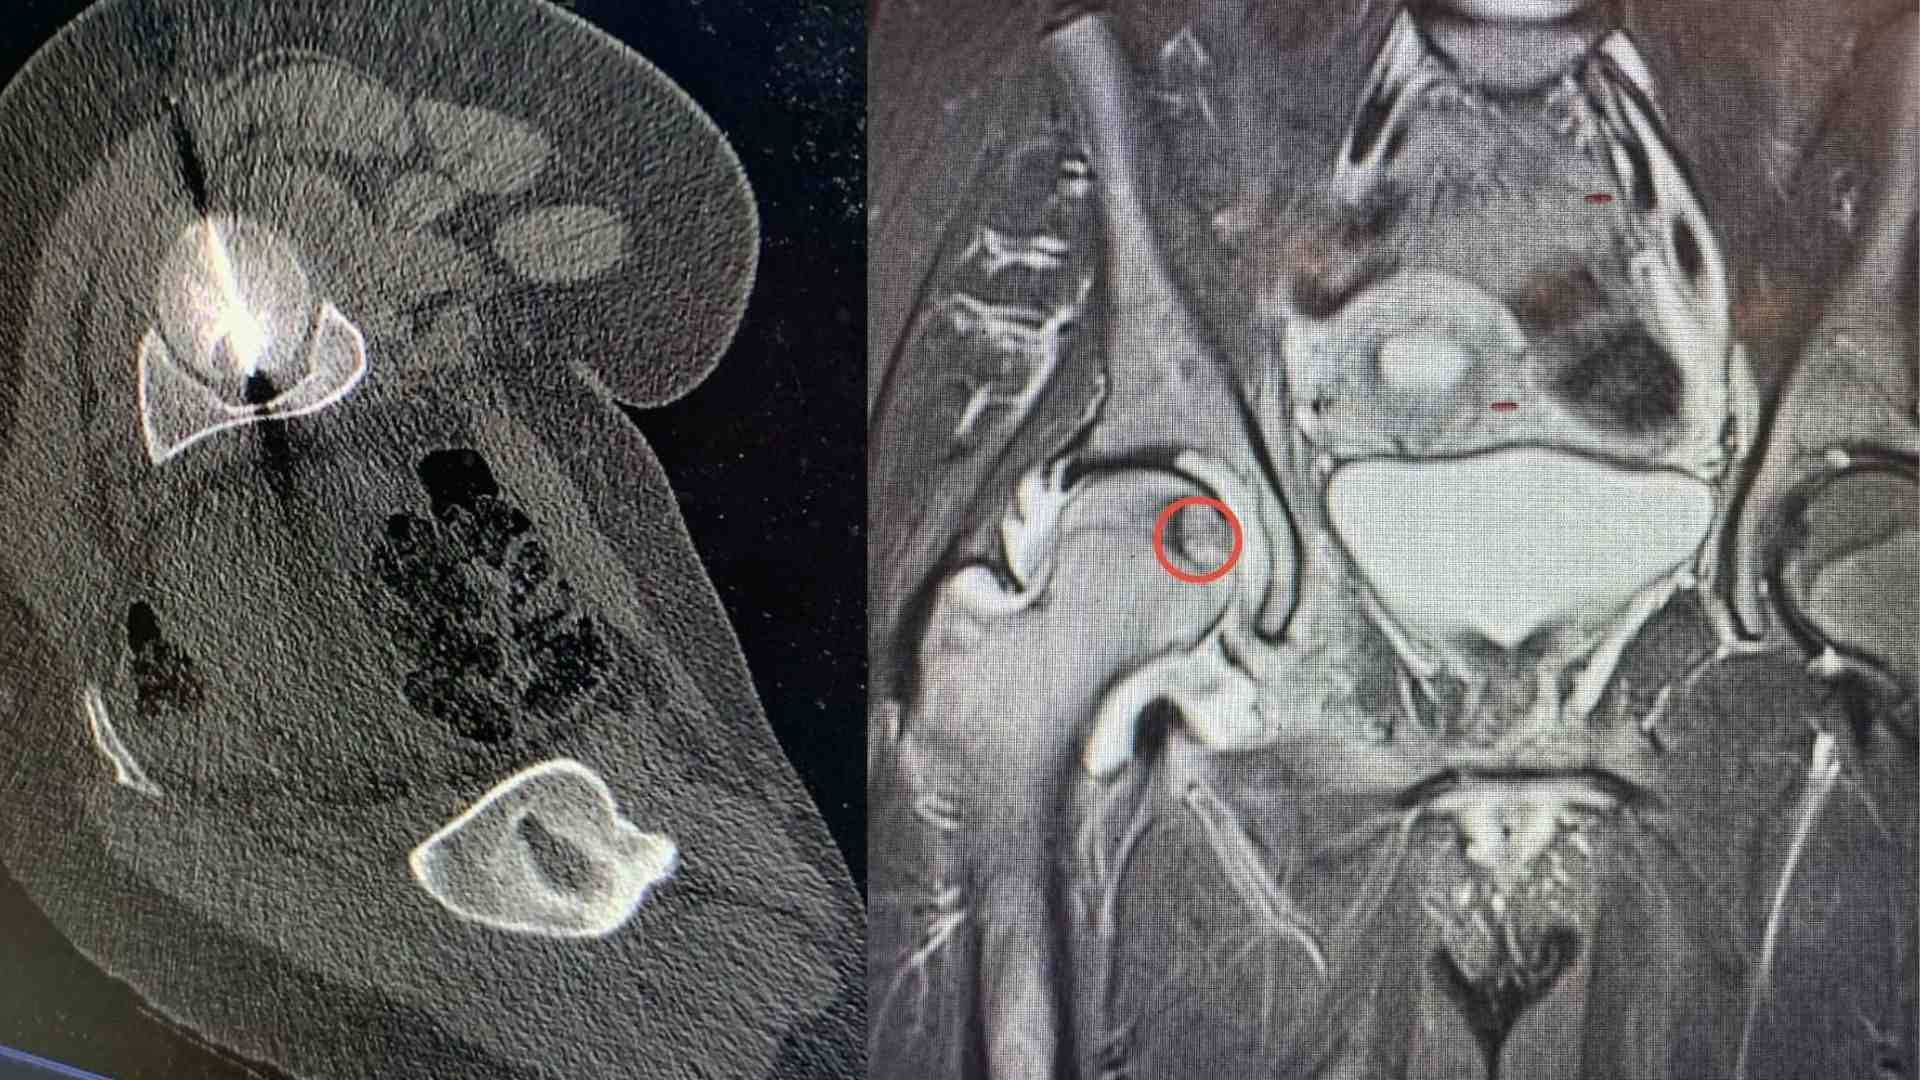

السوسنة - أجرى مستشفى الجامعة الأردنية، تدخلا علاجيا متقدما في قسم الأشعة، استطاع من خلاله فريق طبي متعدد الاختصاصات معالجة ورم عظمي في موقع شديد الحساسية داخل رأس عظم الفخذ لمريض ثلاثيني.

ويعد هذا الموقع من أكثر المواضع صعوبة في الوصول إليها جراحيا، ما يجعل الخيارات التقليدية محدودة ويزيد من تعقيد التعامل مع الحالة، لاسيما وأن المريض كان يعاني من آلام حادة أثرت بشكل كبير على قدرته على الحركة وممارسة أنشطته اليومية.

وبين البطوش، أن الفريق الطبي نجح في الوصول إلى مركز الورم بدقة عالية باستخدام تقنية التصوير الطبقي المحوري (CT Scan)، تلا ذلك إجراء الكي بالتقنية الحرارية باستخدام المايكروويف، وهي من أحدث التقنيات العالمية في علاج أورام العظام دون الحاجة إلى التدخل الجراحي المفتوح.

وأضاف، إن المريض أظهر تحسنا فوريا وملحوظا منذ اليوم التالي للإجراء، ما يعكس دقة التقنية وفاعليتها في استهداف الورم وتخفيف الألم بسرعة وتمكين المريض من استعادة الحركة بصورة أفضل.